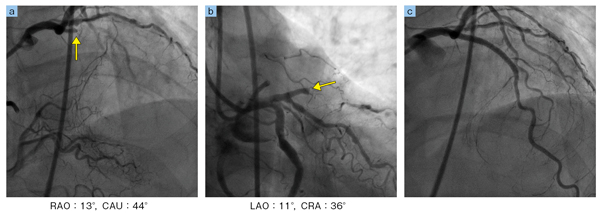

■AlluraClarity FD10/10による症例画像

LADの慢性完全閉塞病変(矢印で閉塞)。細小血管のディテールも明瞭に描出されている。軽くRAO,LAOがかかっているが,ほぼ体軸に沿った直行する2方向で閉塞部を確認できる(a,b)。そのため容易に通過拡張が得られている(c)。